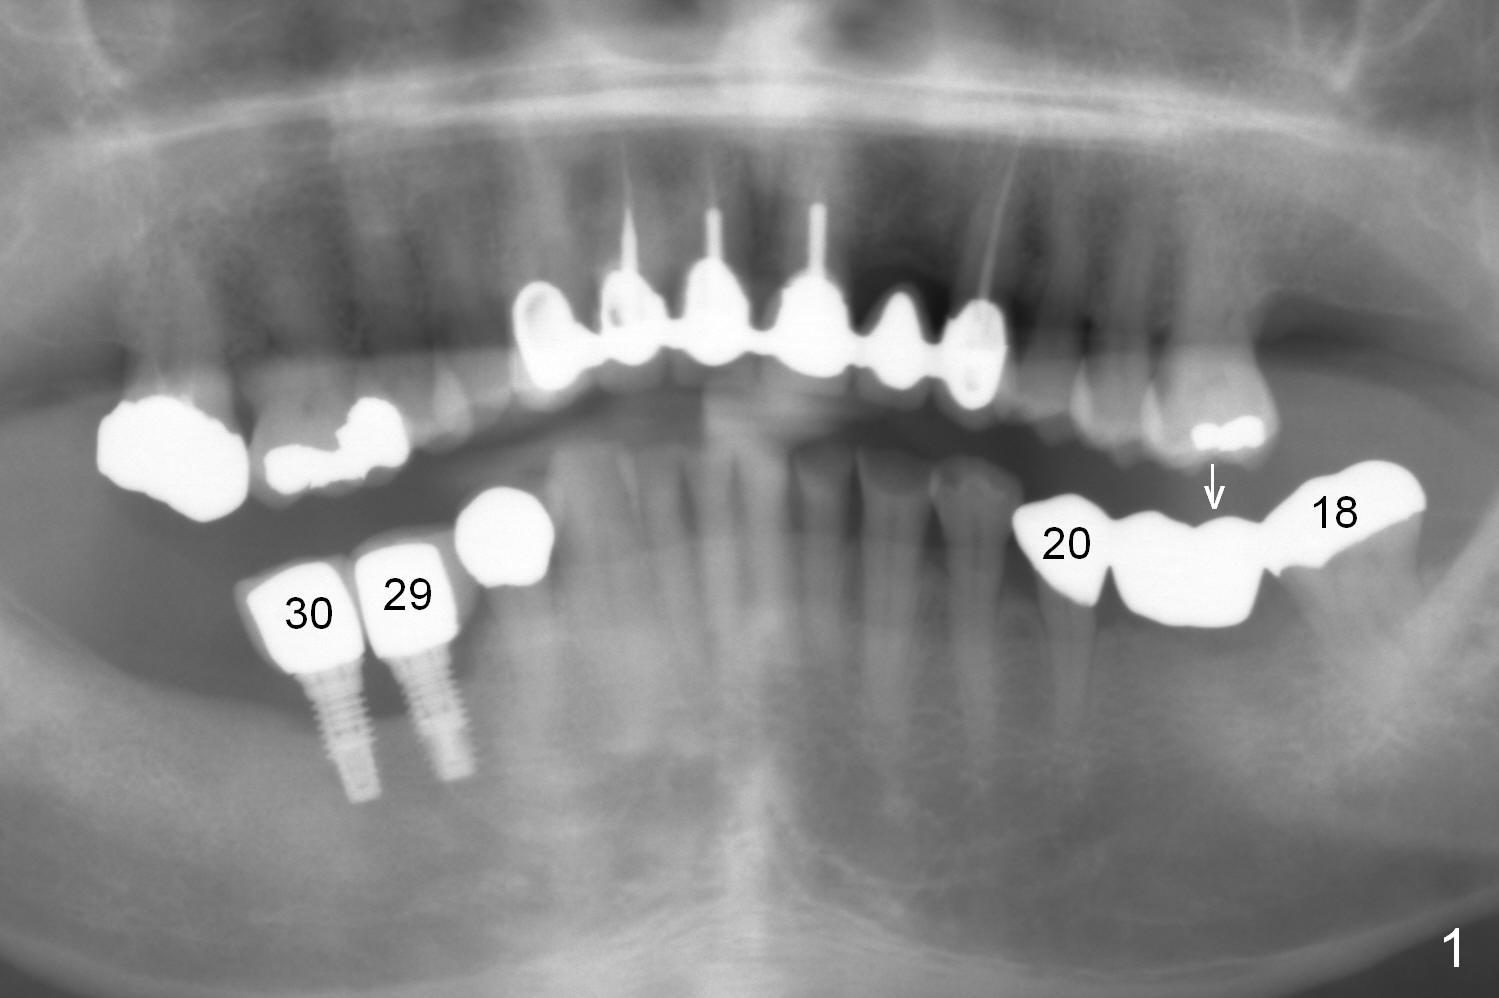

A 71-year-old man has lost an implant at #29 (Fig.1 (taken 3 years earlier)). CT shows that the implant at #30 is failing. The biggest challenge of re-placing implants at the lower right is lack of keratinized gingiva. Gingival graft is mandatory.

The abutment tooth at #18 is symptomatic with gingival recession (Fig.2). It appears that it is overloaded due to pressure from the tooth #14 (Fig.1 arrow). An implant at #19 should be able to alleviate the pressure on the tooth #18.

The 3-unit bridge (#18-20 in Fig.1) will be sectioned (Fig.2 red lines) with the pontic of #19 to be removed. The ridge top is narrow (Fig.3). To place a 5 mm UF implant, the triangular ridge top should be reduced (result).